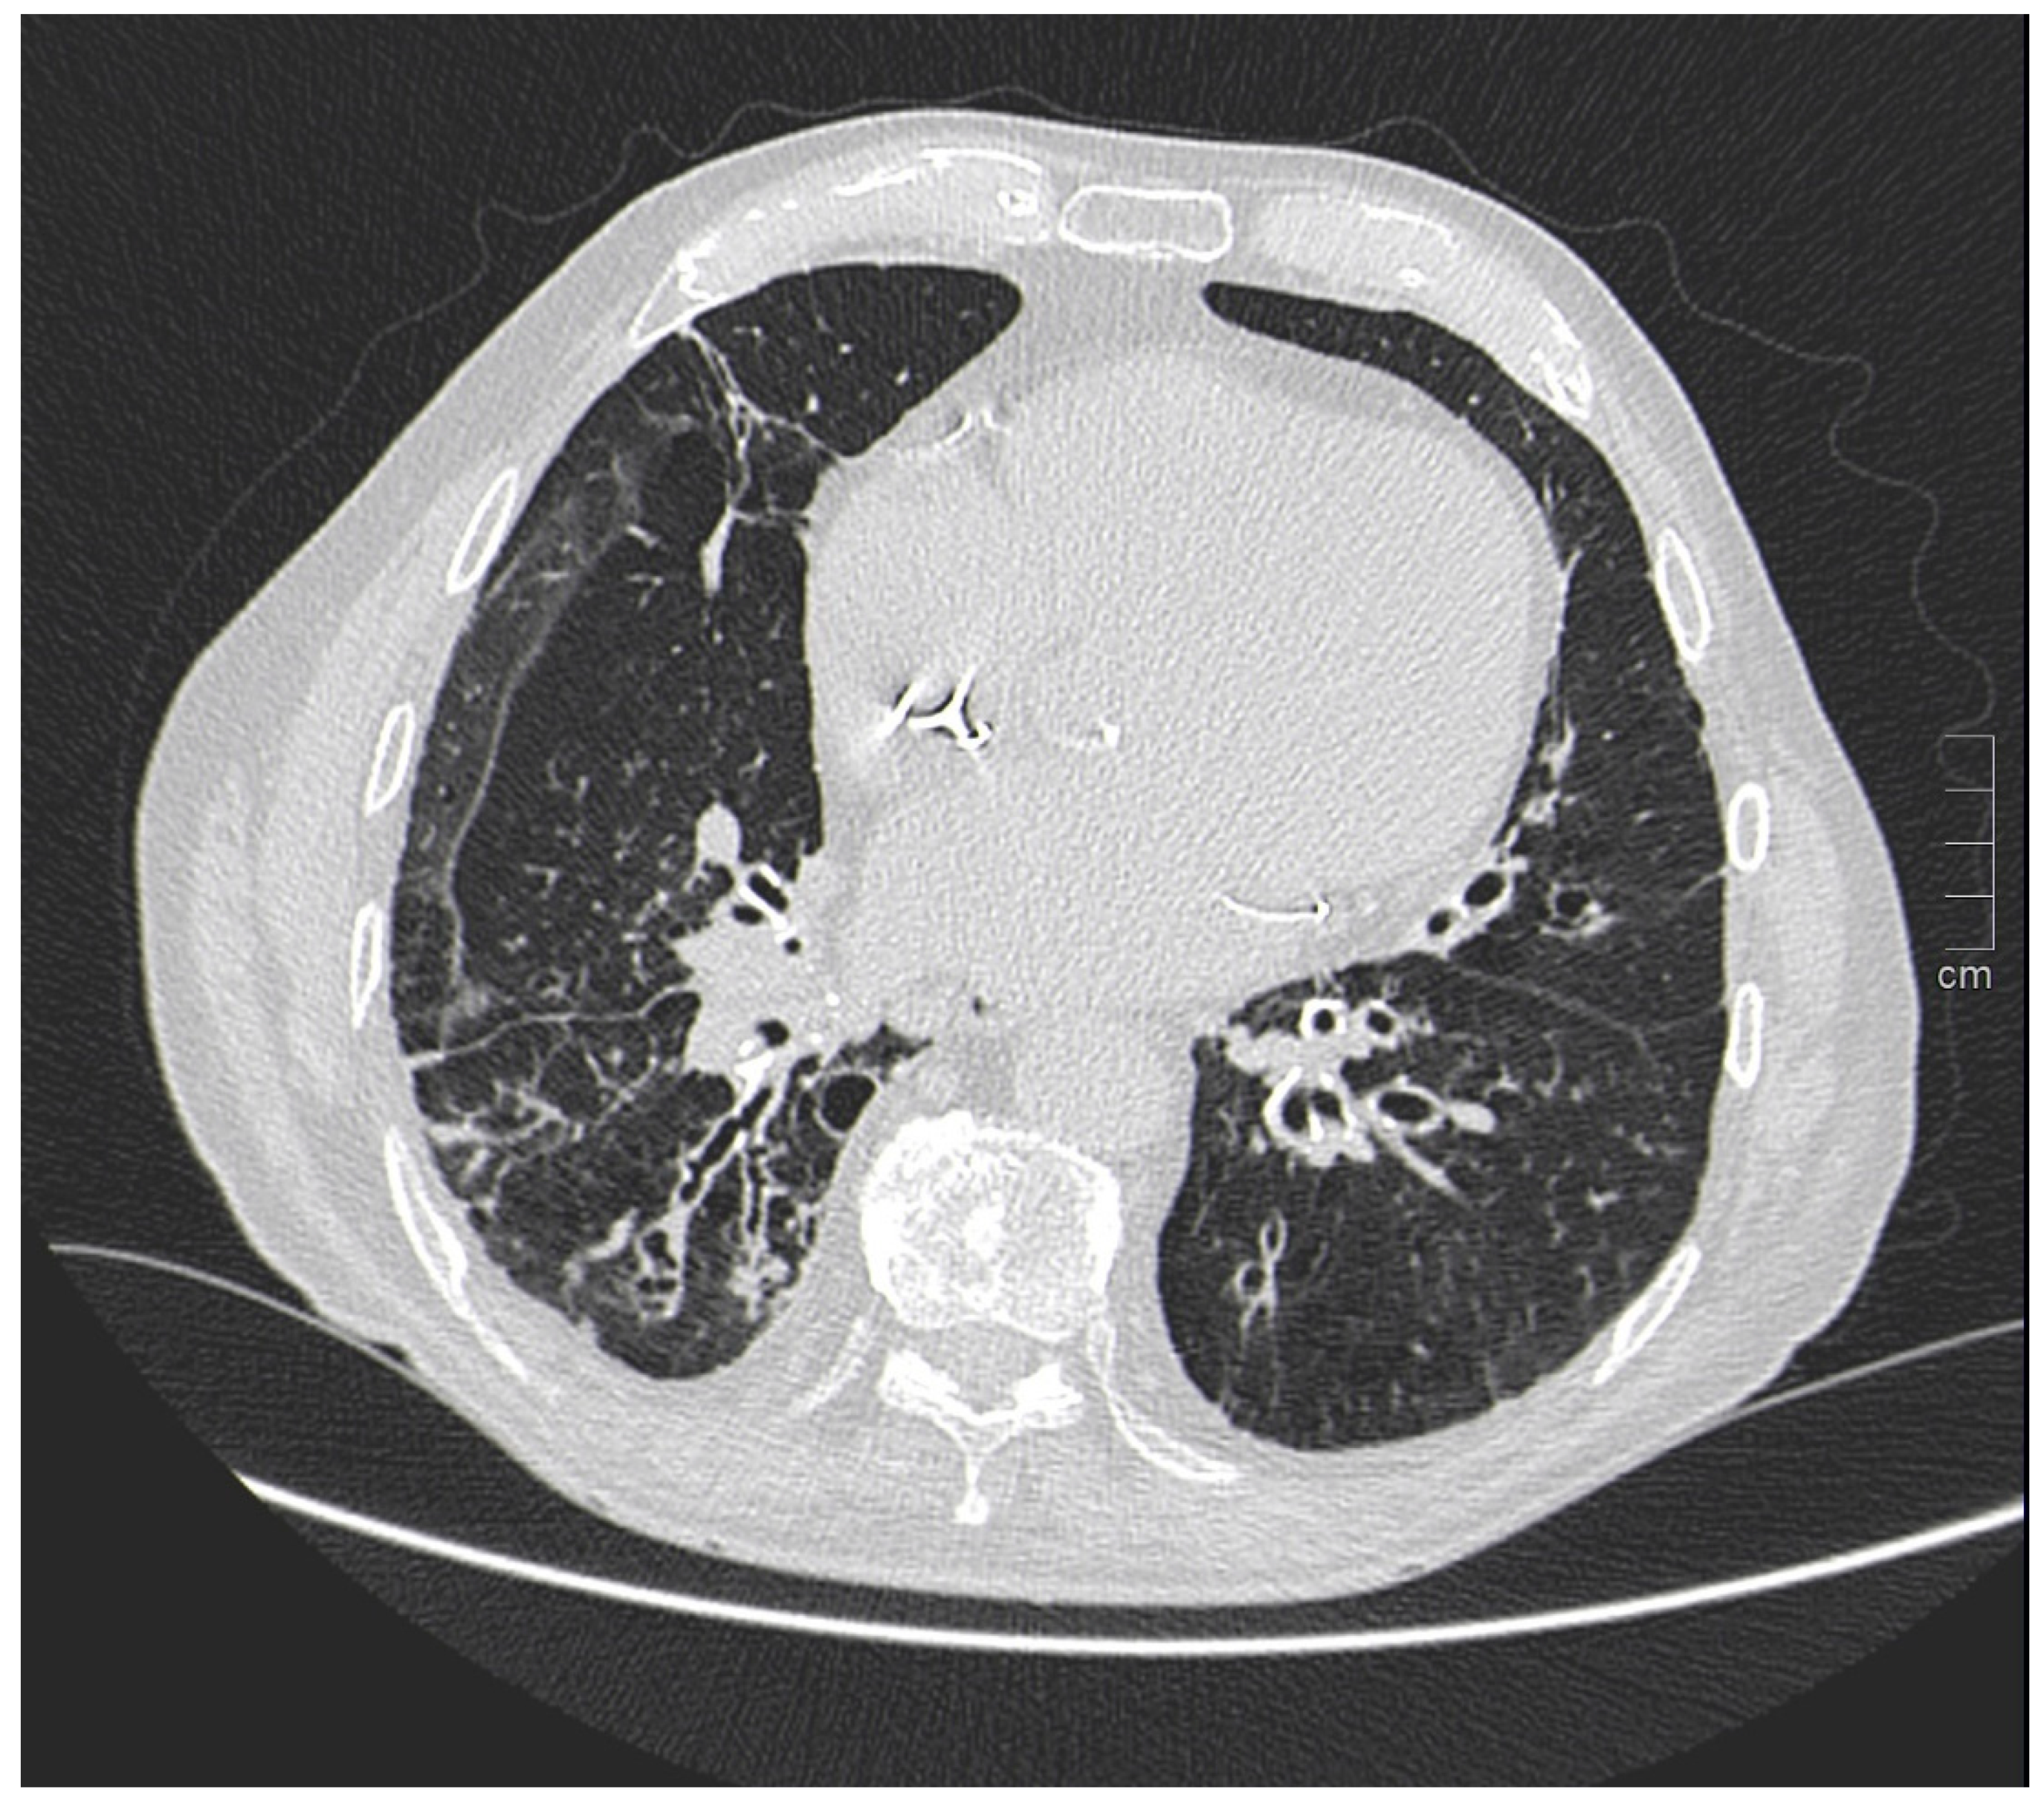

One study [103] investigated the survival of women with CF compared with men and showed that survival in the female population with CF is lower than that of men by about 5 years. Underlying this discrepancy is a different and higher anatomic-structural involvement on high-resolution chest CT (HRCT) in women with CF compared with men (Figure 3). Indeed, higher scores were recorded in women regarding the extent of bronchiectasis, involvement of bronchial branches, and severity of bronchiectasis, thus illustrating a virtually generalized involvement of the bronchial tree, as well as regarding air entrapment. This resulted in more frequent exacerbations, worse functional and nutritional outcomes, deterioration of quality of life, and greater structural damage in the female population.

Figure 3.

A woman and a man with CF with different and higher anatomo-structural involvement at HRCT in women with CF compared with men. (A) Diffuse cystic-varicoid bronchiectasis, with diffuse wall thickening and mucous plug (white arrow) in a young woman patient with cystic fibrosis. (B) Bronchiectasis with thickened walls (white arrow), especially in the medium-lower pulmonary lobes in a male patient with cystic fibrosis.

IPF, on the other hand, is a male-dominated disease. In international cohorts, males account for about 70% of all IPF cases. A recent study found that clinical physicians rarely assign the diagnosis of IPF to women and that gender is the most discriminating pre-test diagnostic probability criterion according to them [103].

IPF is a chronic, irreversible, disabling disease with a fatal outcome characterized by a progressive decline in lung function. It is associated with a radiological pattern of usual interstitial pneumonia (UIP). In the literature, women have shown less fibrotic alterations than their male counterparts at HRTC (Figure 4).

Figure 4.

(A) Diffuse ground glass opacities with reticular thickening of the subpleural interstitium (white arrow), together with traction bronchiectasis in a case of pulmonary fibrosis with UIP pattern and smoking-related interstitial lung disease (ILD) in a female smoker. (B) A typical UIP pattern in a male smoker with idiopathic pulmonary fibrosis, together with diffuse ground glass opacities (white arrow) during an acute exacerbation.

A French multicenter prospective study [104] explored gender differences in an IPF cohort over a 5-year follow-up period. The cohort included 51 (22%) females and 185 (78%) males with a mean age at diagnosis of 70.1 ± 9.20 and 67.4 ± 10.9 years, respectively. At presentation, honeycombing and emphysema at HRCT were less common in females: (n = 40 (78.4%) vs. n = 167 (90.3%), p = 0.041) and (n = 6 (11.8%) vs. n = 48 (25.9%), p = 0.029), respectively. Fewer women than men also underwent transplantation during follow-up (n = 1 (1.96%) vs. n = 20 (10.8%), p = 0.039).